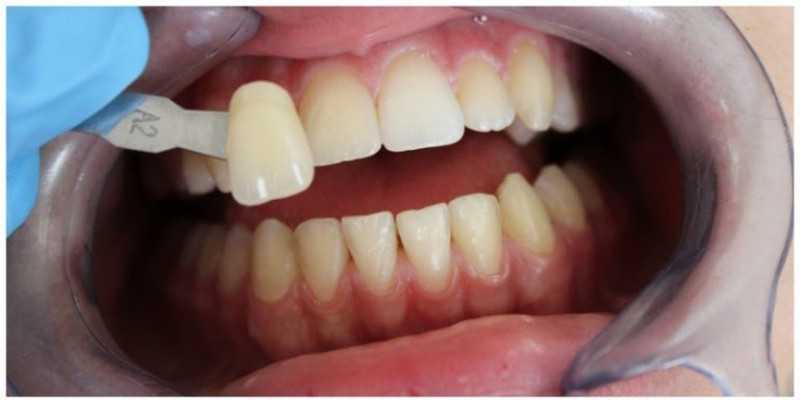

Центр имплантации и протезирования ЗУБЫ БЕЗ БОЛИ

Отбеливание Zoom 4

В данном клиническом случае представлен выраженный дисколорит зубов за счёт пигментации и проведённого около 5 лет назад эндодонтического лечения зуба 1.1.

Доктор: Гатиятуллин Тимур Фанисович